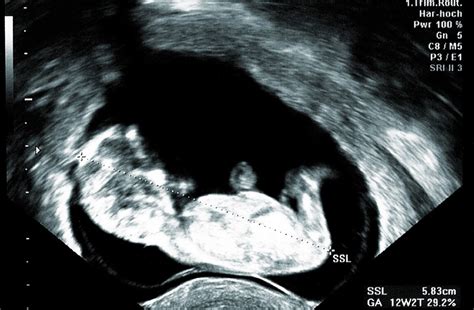

Lekári sledujú rast plodu pomocou ultrazvukového vyšetrenia, nazývaného fetálna biometria. Ide o meranie anatomických vlastností plodu, ktoré pomáha posúdiť jeho vývojový proces a odhaliť prípadné odchýlky.

- CRL (Crown Rump Length): Temeno-kostrčová vzdialenosť. Meria sa od hlavičky po kostrč plodu a používa sa do približne 20. týždňa tehotenstva.